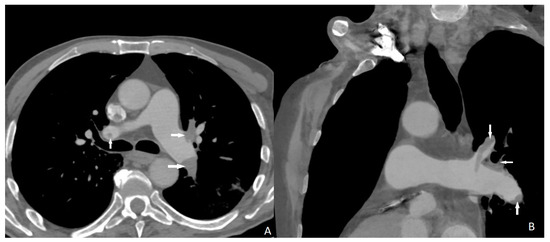

All of the aortic dissection cases were successfully detected with quadruple-rule-out CT angiography protocol (Figure 4). Sensitivity, specificity, and positive and negative predictive value of quadruple-rule-out CT for aortic dissection were 100% (95% CI). Cohen’s coefficient of variation (ĸ value) for the presence of aortic dissection was 1 (perfect).

Figure 4.

Stanford type B aortic dissection affecting both ascending and descending aorta (arrows). ((A) sagittal; (B) coronal).